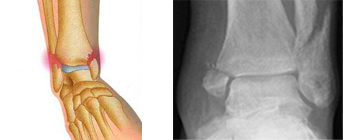

La fracture de cheville concerne la partie basse du tibia, du péroné, ou les deux, au niveau des « malléoles ». C’est une fracture articulaire, ce qui signifie qu’elle doit être parfaitement alignée pour pouvoir consolider sans séquelles car elle expose au risque d’arthrose ultérieure de la cheville.

Il sera confirmé par des radiographies qui permettent de localiser la ou les fractures et de décider du traitement à entreprendre.